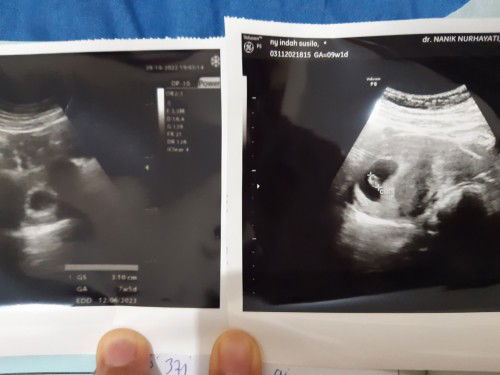

Hasil USG bidan dan dokter beda usia

Hai bund, USG di bidan dan dokter beda usia. Sabtu kemarin USG di bidan usia 7w 5d baru keliatan kantongnya aja. Hari ini USG di Spog usianya mundur seminggu jadi 7w 1d tapi Alhamdulillah sudah keliatan djj nya 🥰. Hpht usia 9w tp USG 7w, it's okay beda seminggu yang penting debay sehat 🥰

Hasil USG 7w 5d

Hasil USG pertama usia 5w blm kelihatan apa2, 2mingguan balik USG lagi alhamdulillah sudah kelihatan kantung janinnya. Meskipun hpht 8w 3d tpi USG nya 7w 5d selang hampir 1minggu it's okay yg penting bidan bilang sehat dan normal. Minta doanya ya bund smoga sehat dan lancar sampai persalinan. Saya doakan juga smoga ibund2 kehamilannya sehat dan normal, dilancarkan dan dimudahkan sampai persalinan 🤲🥰